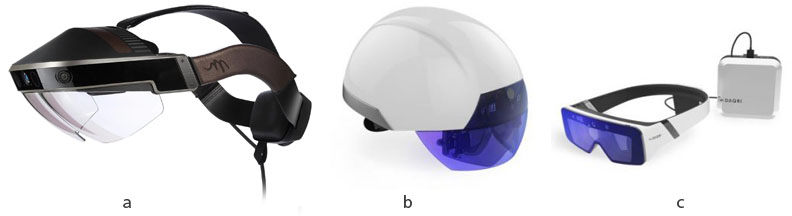

As progress has been made on virtual reality (VR) and augmented reality (AR) devices, current headsets have demonstrated higher quality and lower prices. The most popular AR platform, Microsoft HoloLens [1], presented in Figure 1 , offers an advanced development and experimental platform. VR and AR devices offer 360∘ vision as well as haptics and interactions using mechanisms unbound by traditional machine-human interaction devices (like keyboards, pointer devices, controllers).

Meta [80], presented in Figure 3(a), is a tethered HMD, i.e. it needs to be connected to a PC through a physical cable and is conceived to work in a stationary context which means the user can’t walk around in the real world environment while wearing it. This limitation determined us to exclude it for this project, although it has a far larger FOV than HoloLens, and it can directly leverage the PC’s computing power.

DAQRI models, illustrated in Figure 3(b, c) were conceived mostly for an industrial environment usage and were eliminated for physical characteristics improper for our project (either helmet or using a cable) and because they provide only gazing as a control option (no hand gestures for example). It was also argued that the Daqri Helmet was presenting some tracking problems [81]. We are not aware if collaborative synchronization has been implemented yet, or if the new 2018 Daqri glasses model fares better than HoloLens in regards to tracking performance, however, the Daqri glasses are unsuitable for our scenario as the headset makes use of an external mini-computer weared on the hip and connected through a cable.